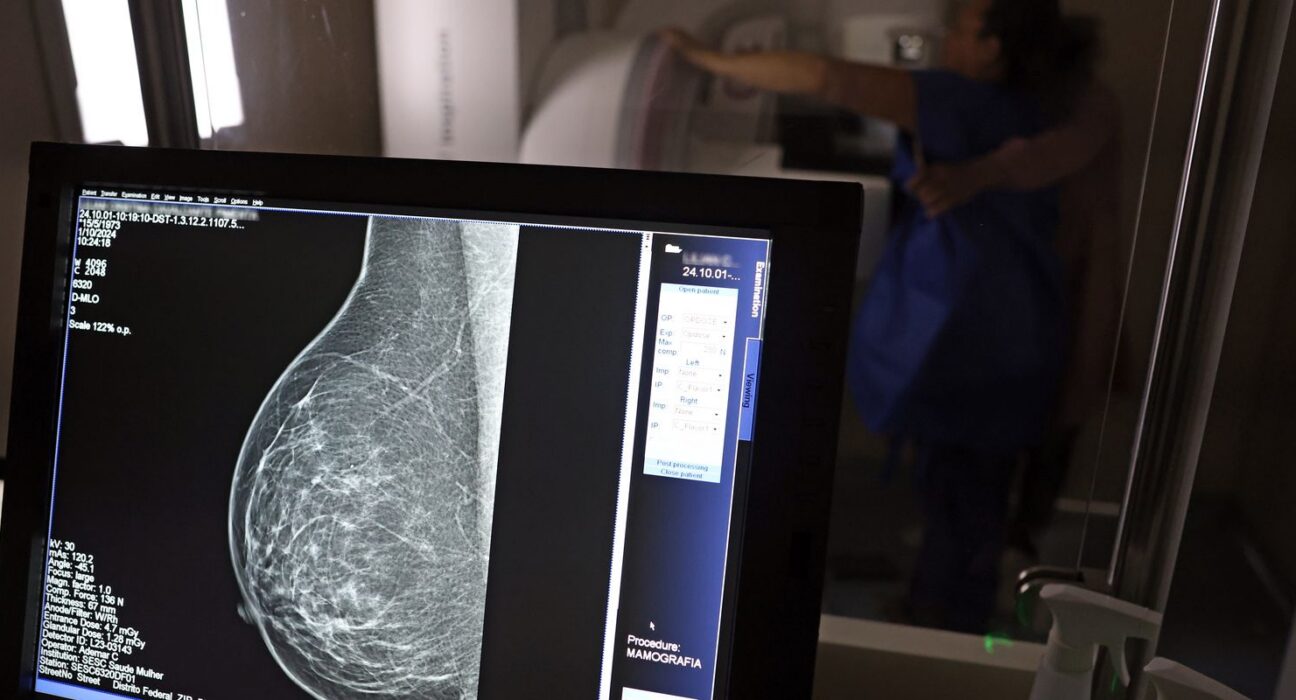

O direito já estava incluído na CLT desde 2018. A partir de agora, as empresas passam a ser obrigadas a divulgar essa informação, além de outras relacionadas a campanhas oficiais de vacinação contra o HPV e sobre o acesso a serviços de diagnósticos de cânceres de mama, próstata e de colo do útero.

O texto estende o uso das folgas também para a realização de exames preventivos do HPV, além dos de câncer que já estavam previstos na legislação anterior. A a Lei 15.377 foi sancionada pelo presidente Luiz Inácio Lula da Silva, e publicada na edição do Diário Oficial da União (DOU).